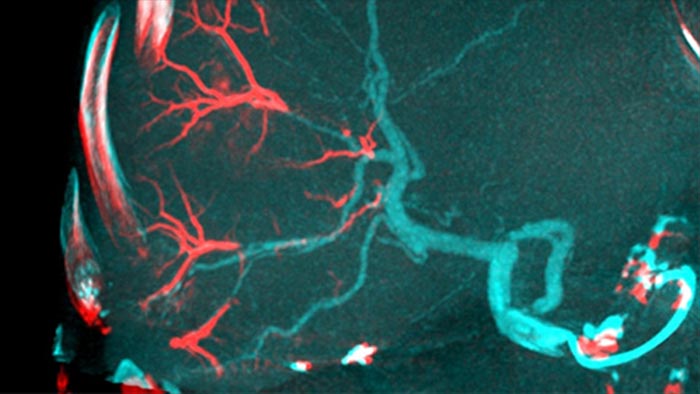

Cobertura de todo el hígado con la THC abierta

Al abrir el arco a la izquierda del paciente, la THC abierta permite el posicionamiento fuera del centro de la mesa del paciente y, por lo tanto, un mejor centrado del campo de visión3-4.Aumenta significativamente la cobertura de imágenes para ayudar a visualizar los tumores en la periferia del hígado.4.